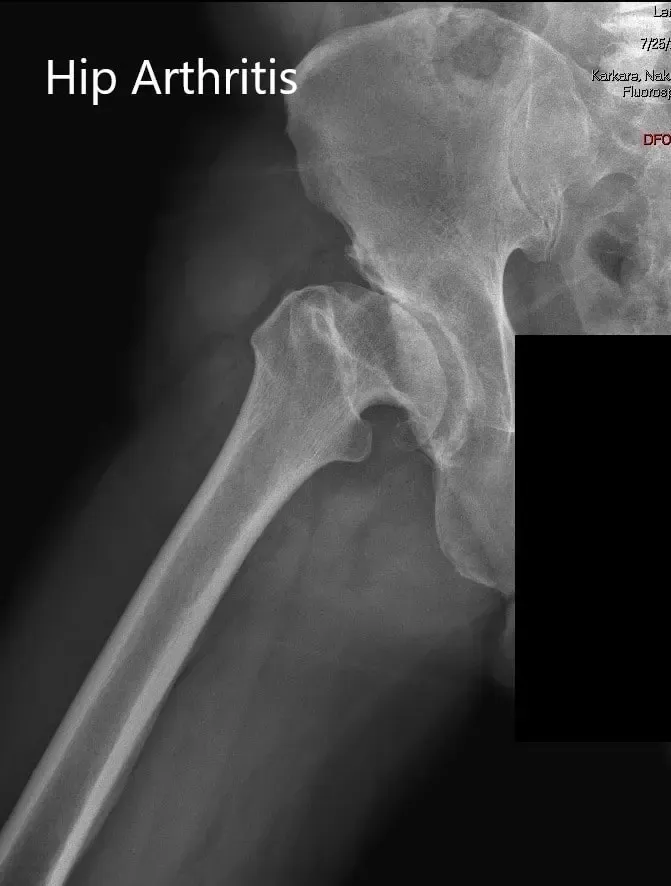

AP and lateral views of the right hip joint

Imaging revealed markedly deformed right femoral head and impacted the femoral neck. There were severe degenerative changes of the right hip.